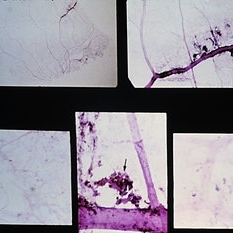

Left: Gross appearance of a funnel-shaped detachment of the vitreous. It remains attached at its base and at the optic nerve head. Center and right: Appearance of ring-shaped vitreous condensation, formerly attached at the optic nerve head. Such condensations can account for the visual symptom of floaters. (E.P. No. 21811)

Condition/keywords: detachment, operculum, vitreous